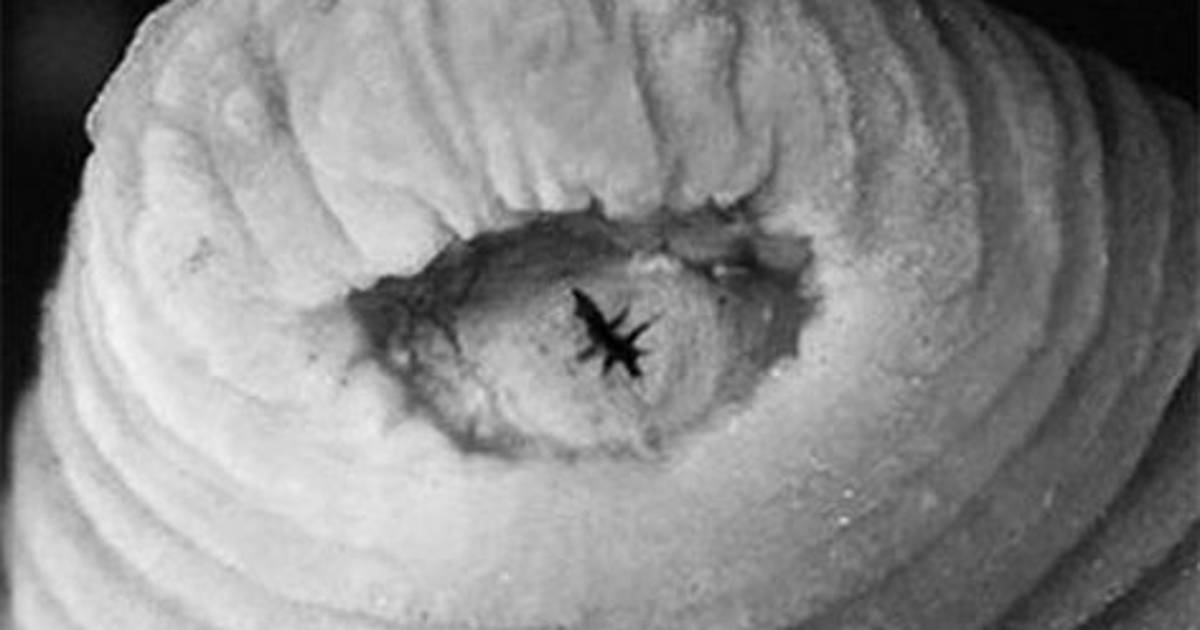

La sanguijuela, a la que se denominó 'Tyrannobdella rex', medía 44,5 milímetros y tenía una mandíbula con grandes dientes.

Los padres de la niña notaron un gusano negro que se movía dentro de su fosa nasal derecha por lo que buscaron atención médica.

En el hospital de Chanchamayo, los médicos hicieron un examen físico a la paciente y lograron sacar el gusano sin provocarle sangrado para luego preservar la especie en etanol.